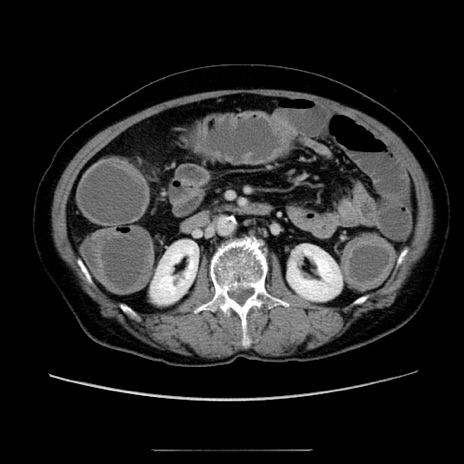

冠状断像

【症例】70歳代女性

【主訴】お腹が張る

【現病歴】1週間くらい前から腹部膨満の自覚あり。昨日夜から増悪したため、本日救急外来受診。

【身体所見】意識清明、BT 36.5℃、BP 165/106mmHg、HR 80bpm、SpO2 98%、腹部:膨満、軟、自発痛・圧痛なし、触診にて不快感あり、腸蠕動音:減弱

【データ】WBC 12600、CRP 1.04